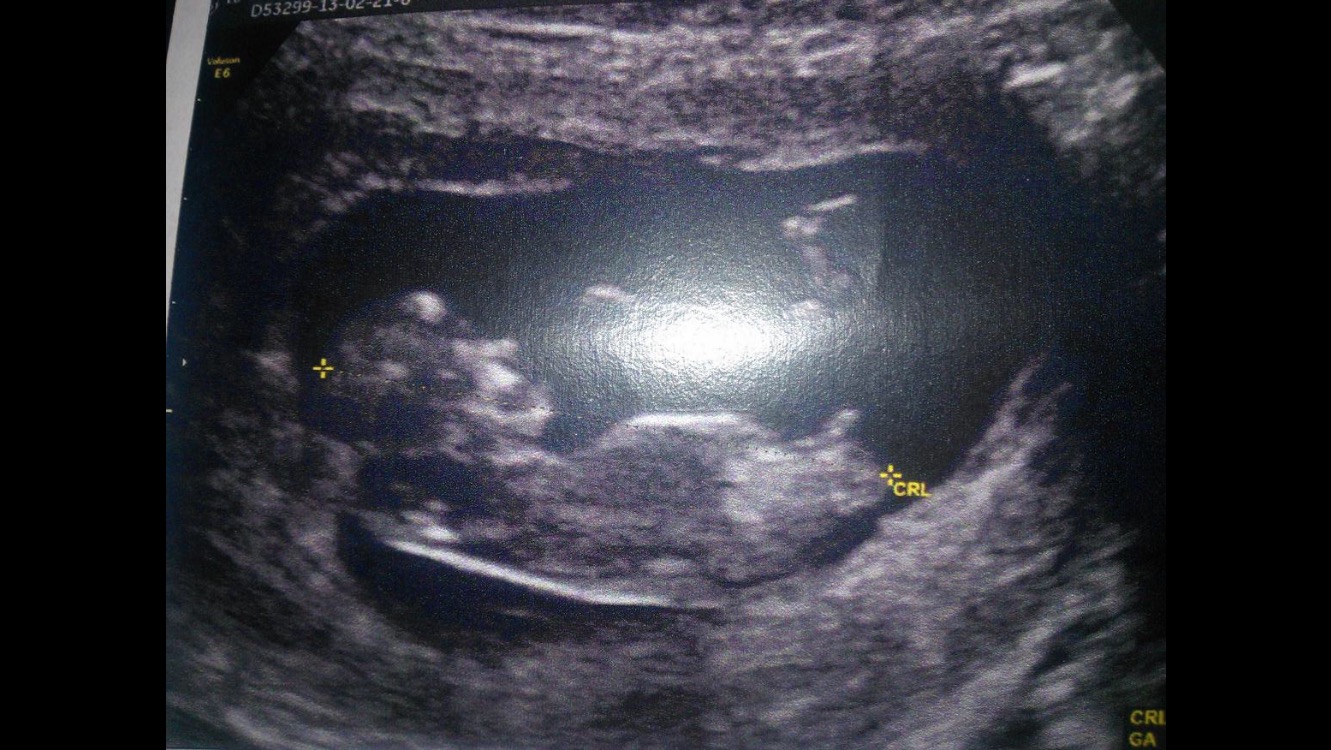

this is de US of my friend at 12w6d.

Boy! Nub pointing up

My goodness I think that's the clearest boy nub I've ever seen! Hope she wanted to hear boy! :) x

holy crap thats a boy he decided to show it off loud and proud at an early date!